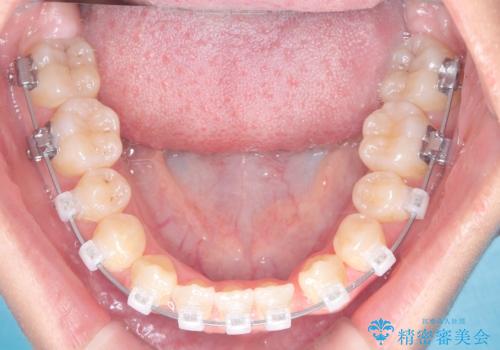

安全かつ確実に抜歯スペースを閉じ、咬み合わせを完成させるため、マウスピースから**ワイヤー矯正(マルチブラケット装置)**へ切り替えるリカバリープランを提案しました。

装置の変更と歯肉への配慮: ワイヤー矯正は歯の根(歯根)を平行に移動させる「歯体移動」を得意としています。本症例では、歯肉退縮を防ぐために、歯の傾きを精密にコントロールしながら抜歯スペースを閉じる必要がありました。ワイヤー装置を用いることで、インビザラインでは難しくなっていた三次元的な細かい調整を可能にしました。

リカバリーのプロセス: 適合が悪くなったインビザラインを一旦中止し、ブラケットを装着。停滞していた歯の移動を再開させ、上下の正中(中心)や奥歯の咬み合わせを一つひとつ整えていきました。